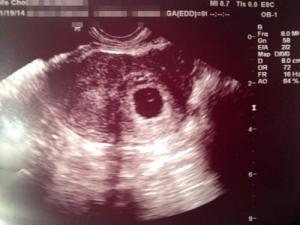

I had my ultrasound today. I have attached a photo of the image I brought home.

There is a clear sac and a yolk sac present but no visible heartbeat yet. The measurements of the sac they say are between 5 weeks, 4 days and 6 weeks, 0 days. The baby has implanted in the left side of my bicornuate uterus, which makes sense as I am thinking the ablation was performed on the right side of the uterine cavity.

Hoping this is a good start to a healthy, full-term, post-ablation pregnancy.